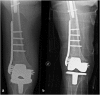

Osteoporotic distal femur fractures in the elderly: peculiarities and treatment strategies

Distal femur fractures account for 4-6% of osteoporosis related fractures of the femur in the elderly population. They represent a relevant cause of morbidity and mortality in the geriatric population with a reported 1-year mortality reaching 30%. Non-displaced fractures or even displaced fractures in patients with high operative risk can be treated conservatively. However, operative treatment is the most widely accepted management option for displaced fractures. The advantage resides in early mobilization and weight-bearing, reducing risks related with a prolonged immobilization when compared with conservative treatment. On the other hand, the intrinsic difficulty of fixing an osteoporotic bone is a major concern. The presence of osteosynthesis devices or prosthetic implants in the femur can make the surgical treatment more challenging, sometimes limiting therapeutic options. Aim of the present paper is to review the most recent literature about osteoporotic distal femur fractures in the elderly, including periprosthetic and other hardware related fractures, to highlight current evidence on management options and related results as a guide for the daily clinical practice.